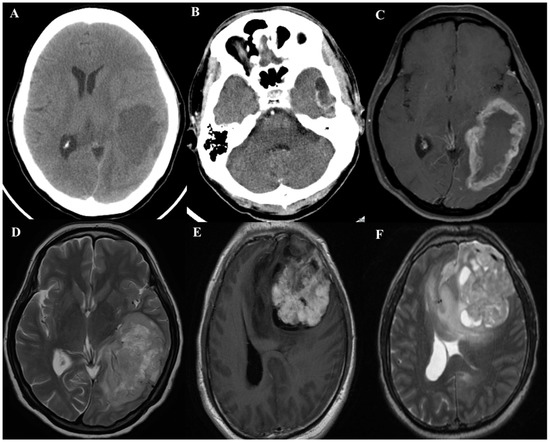

2. Clinical Characteristics of GBM